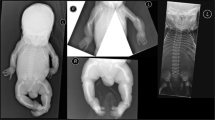

The six patients were from six distinct families, originating from Turkey (three patients, consanguineous parents), from the Netherlands (two patients) and from Iran (one patient, consanguineous parents). They presented with pre- and postnatal short stature (< −3 SD), dislocation of large joints, advanced carpal ossification, monkey wrench appearance of the proximal femora in the first months of life, abnormal vertebrae, luxation of knees with genua valga, hyperlordosis or kyphoscoliosis and small epiphyses (Table 1 and Fig. 1). In addition, hypomineralized amelogenesis imperfecta, characterized by yellow–brown enamel with a rough surface, and short and widely spaced tooth crowns, was diagnosed in all six patients (Table 1). Facial abnormalities were present in all patients: a Pierre–Robin sequence (micrognathia, cleft palate and glossoptosis) in two patients, a micrognathia in three other cases and a flat face in the last patient. Additional features observed included a heart defect (one patient), mixed (one patient) and sensorineural hearing loss (one patient), and obesity in the eldest patients. The parents of the Iranian patient have a history of multiple pregnancies that resulted in a spontaneous abortion and neonatal death due to respiratory distress accompanied by micromelia. Two other pregnancies were terminated preterm after the detection of short limbs during ultrasound screening. One of these induced abortions presented an additional cleft palate.

Morphological and skeletal features of SLC10A7-deficient patients. a Skull X-ray at 6 years of age (Patient 5). Note the retrognathia (arrow). b Hip at one year of age (Patient 1). Note the Swedish key appearance of the proximal femur (medial beak and exaggerated trochanters, arrow). c Hand X-rays at 6 months of age (Patient 2). d Hand X-rays at 3 years of age (Patient 3). Note in (c) and (d, the advanced carpal ossification (presence of three ossified carpal centres at 6 months and seven ossified carpal centres at 3 years instead of one and three, respectively, see arrows). e Knee at 3 years 9 months of age (Patient 3). Note the genu valgum (angled in knee) and flat epiphyses (arrow). f Spine X-rays at 1 month of age (Patient 1). Note the coronal clefts and irregular shape of vertebrae (arrow). g Spine and hip X-rays at 9 years of age (Patient 4). Note the kyphoscoliosis. Informed consent for publication of images was obtained from all individuals or the legal guardians of minors. h Localization of the five SLC10A7 mutations relative to the SLC10A7 gene organization (striped rectangles indicate the 5′ and 3′-UTRs)